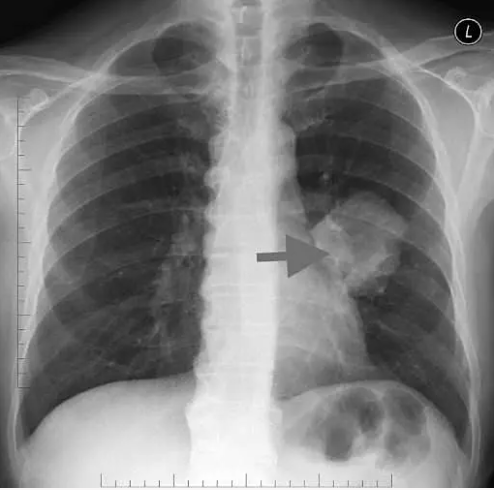

Yapılan incelemeler sonucunda, Xu'nun sağ akciğerinde yaklaşık 1 santimetrelik kitle fark eden doktorlar, bunun kötü huylu tümör olabileceği ihtimali üzerinde durdu.

Doktorlar, kanser olabileceği düşündükleri Xu'ya tam teşhis koyabilmek için akciğer dokusundan parça alarak testler yaptı. Yapılan testler sonucu, doktorların kötü huylu tümör sandığı kitlenin acı biber parçası olduğu anlaşıldı.

Sayin Editör, haber iceriginde sag akcigerde kitleden bahsedilmis ancak filimlerde solda kitle gozukuyor 1 cmden de buyuk gozukuyor. Haber kaynaginizda yanlislik var. Bronkoskopide yiyecek oldugu da belli olur. Bilginize